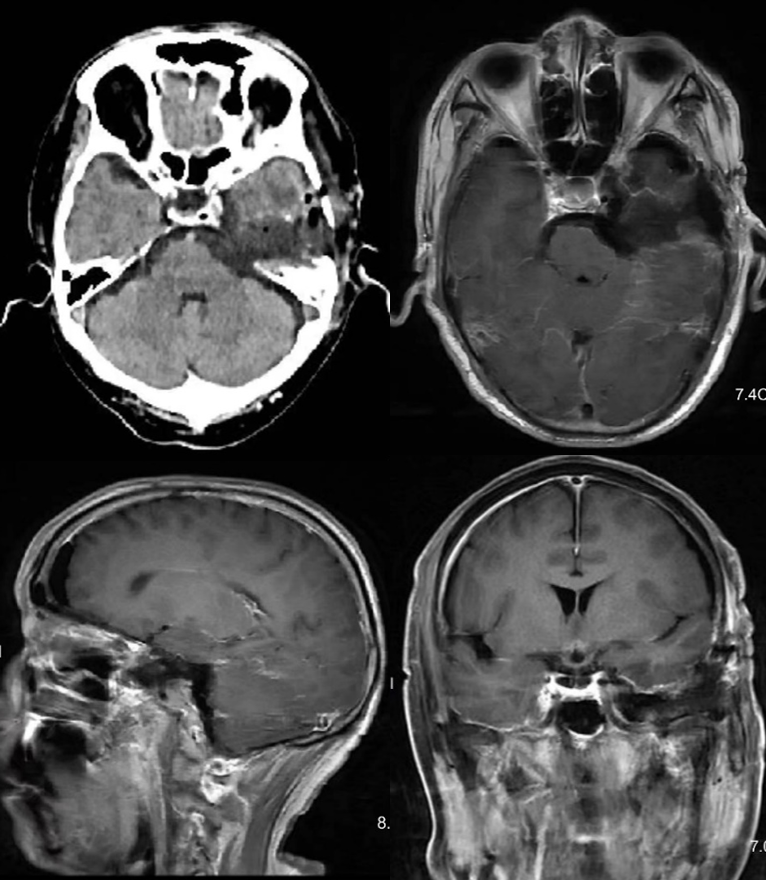

2024年7月复查头颅MRI提示硬膜下血肿已吸收,左侧海绵窦肿瘤快速增大(图4)。

遂收治入院计划手术治疗。由于肿瘤生长迅速,且伽马刀效果不佳,患者术前左眼视力已明显下降仅光感且有暴露性角膜炎,手术以尽可能全切肿瘤及基底、降低术后复发几率为首要目的,由于肿瘤包饶颈内动脉,术中需特别注意避免颈内动脉损伤。经医疗组、科室讨论,决定复合手术下经Kawase入路切除。